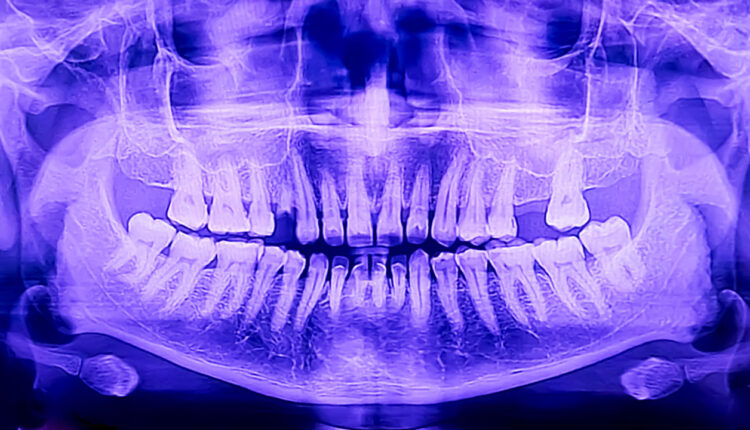

A routine panoramic X-ray turned into a potentially life-saving moment when a dentist spotted suspicious calcifications near a patient’s carotid artery. The discovery ultimately revealed a dangerous blockage, proving once again that the dental operatory can double as an early warning system for systemic health.

Routine new patient exams rarely come with a side of lifesaving drama, but occasionally, dentistry delivers exactly that. During a first visit at Kennestone Dental Designs in Marietta, Gerogia, Nicole Massetti, DMD, MBS, reviewed a standard panoramic radiograph and noticed something that didn’t quite belong: radiopaque calcifications in the region of the carotid artery. While dentists can’t diagnose vascular disease from a panoramic scan, the finding was concerning enough to prompt a strong recommendation that the patient seek medical follow-up.

That advice proved critical. Subsequent medical evaluations revealed a significant carotid artery blockage, estimated between 75% and 80%. The patient ultimately underwent surgery to remove the obstruction before it could lead to a stroke. Calcifications near the cervical vertebrae region may indicate carotid artery atherosclerosis, a finding estimated to appear in roughly 2% to 5% of patients. Careful review of these nondental areas can occasionally uncover serious health risks hiding in plain sight. Click here to read more.